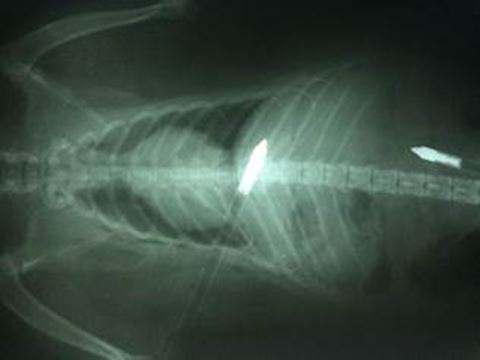

SPCA Seeking Information On Injured Raccoon Shot With Two Arrows

raccoon arrows two ray